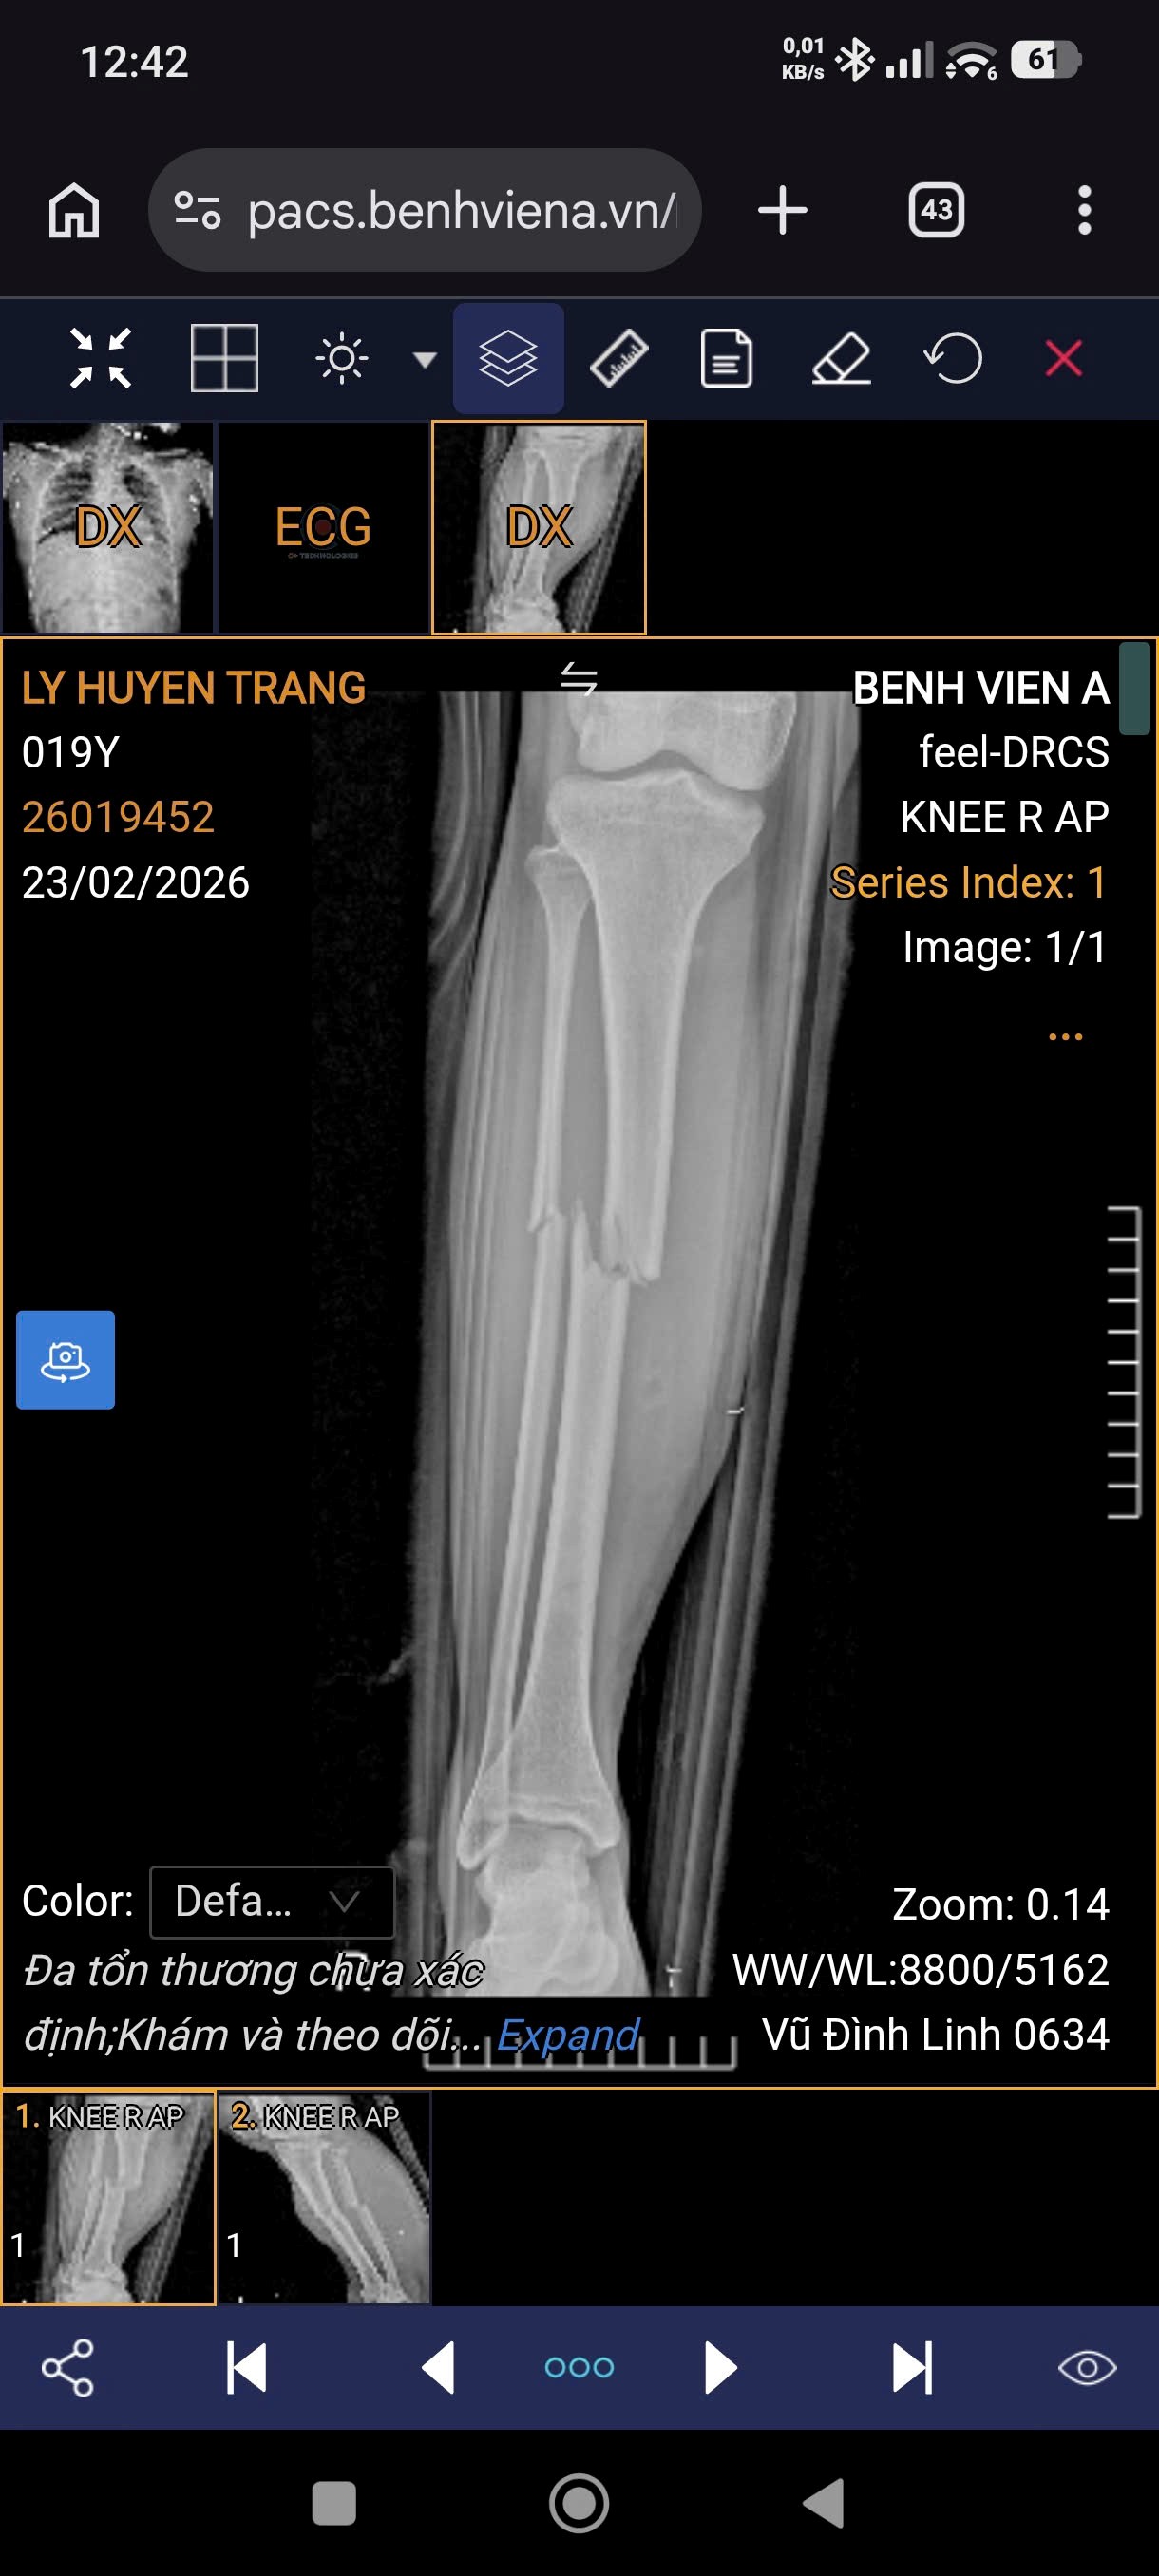

Hình ảnh X-quang bệnh nhân nữ 19 tuổi, gãy 1/3 giữa hai xương cẳng chân phải do tai nạn giao thông.